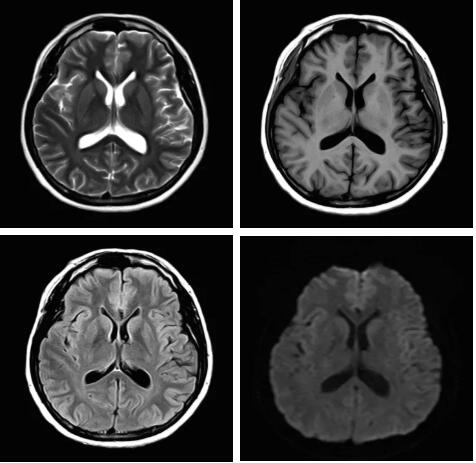

3.Pure射頻成像鏈

從成像源頭的磁體采用鍍膜新磁體高密度薄層鍍膜貼合技術(shù),獲得更好的磁場均勻度,奠定磁共振成像基礎(chǔ);采用3D RSCE微雕梯度精準控制頻率和相位,輸出理想波形,實現(xiàn)渦流的“0”殘余,還原最真實的圖像信息;射頻接收端通過計算機人工智能對信號抗干擾處理,把信號放大并去除梯度、磁場等對信號干擾,再經(jīng)過二次人工智能信號識別,去除噪聲污染獲得純凈的信號;通過Pure射頻成像鏈的優(yōu)化和改進使信噪比提升40%,這是磁共振領(lǐng)域革命性的顛覆和改變。

圖:Pure射頻成像鏈的優(yōu)化和改進使信噪比提升